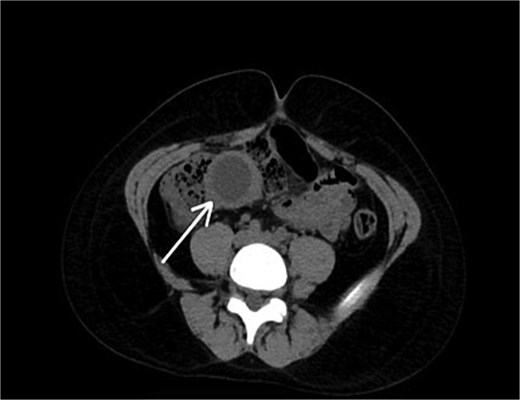

An abdominal ultrasound revealed a cystic mass in the right iliac fossa. Subsequent computed tomography (CT) confirmed the presence of a right abdominal cyst, with the most likely diagnosis being a mesenteric cyst (Fig. 1).

A preoperative axial CT scan of the abdomen and pelvis demonstrates a well-defined, fluid-filled cystic structure adjacent to the bowel.